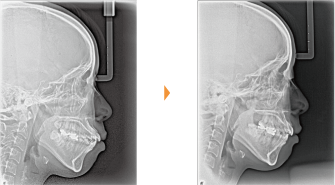

| 主訴 | 前歯が出ている |

| 年齢・性別 | 35歳 / 女性 |

| 治療方針 | 叢生も前歯の突出も大きいケース。小臼歯抜歯だけでは改善できないため、大臼歯の抜歯も行なった。 |

| 抜歯部位 | 上下顎左右小臼歯、左上第1大臼歯(計5本) |

| 使用装置 | マルチブラケット装置 |

| 治療期間 | 36か月 |

| リテーナー | 上顎インビジブル、フィックス、下顎インビジブル |

| 費用 | 885,000円(税別) |